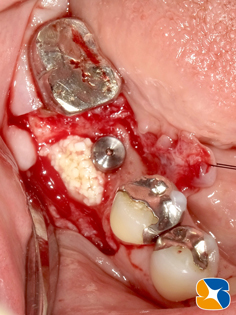

砕けた歯根を抜歯した後、続けてインプラントを同日に移植しました。

CGFと骨の誘発材(β−TCP)を使って、アゴ骨と歯肉の早期再生・回復を促しました。

使用インプラント:スプライン直径3.75㎜、高さ11.5㎜